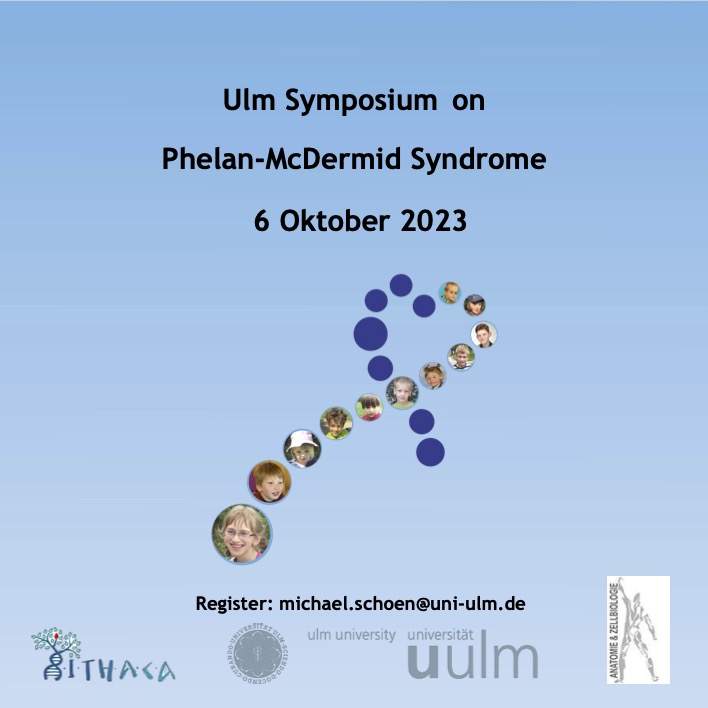

🚨 3rd Phelan-McDermid Symposium, Oct 5-6th, hosted by Anatomy UUlm at Universität Ulm , supported by PMS Family Association (PMD-Gesellschaft e.V.). Join us for vital discussions on PMS research and guidelines. More detail and registration see below👇 #22q13 #PMS